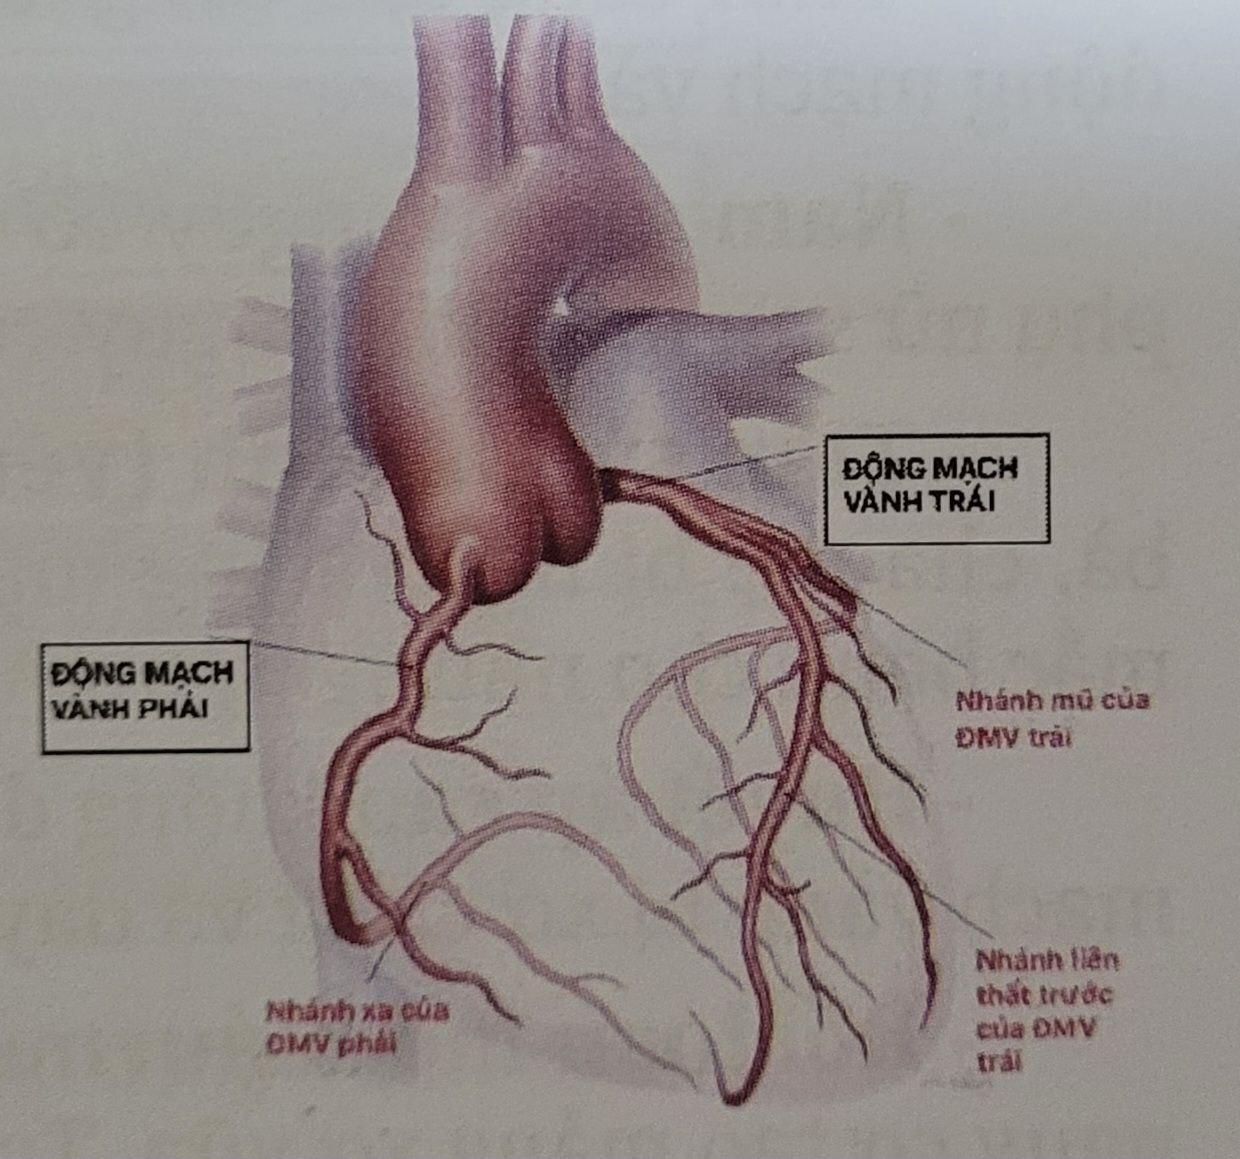

Các động mạch vành nuôi tim

Các động mạch vành nuôi tim

Tim là một trong những bộ phận quan trọng nhất cơ thể, giữ nhiệm vụ bơm máu đến nuôi tất cả các cơ quan và bộ phận trong cơ thể. Để thực hiện tốt việc đó, tim cũng cần được nuôi dưỡng bằng một hệ thống mạch máu riêng của tim. Hệ thống mạch máu chuyên trách này được gọi là động mạch vành.

Các động mạch vành cung cấp máu, oxy và chất dinh dưỡng cho tim. Sự tích tụ của mảng bám (mảng xơ vữa) có thể làm thu hẹp các động mạch vành này, làm giảm lưu lượng máu đến tim. Khi lưu lượng máu động mạch vành giảm đáng kể cơ tim sẽ không được cấp máu đầy đủ gây ra cơn đau thắt ngực.